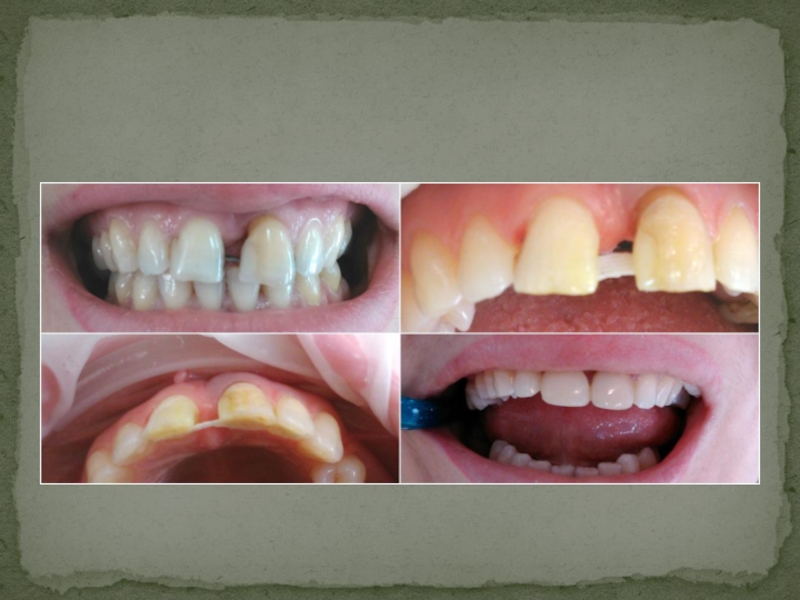

Слайд 22Пример шинирования зубов при помощи стекловолоконной ленты

Пример шинирования зубов при помощи стекловолоконной ленты